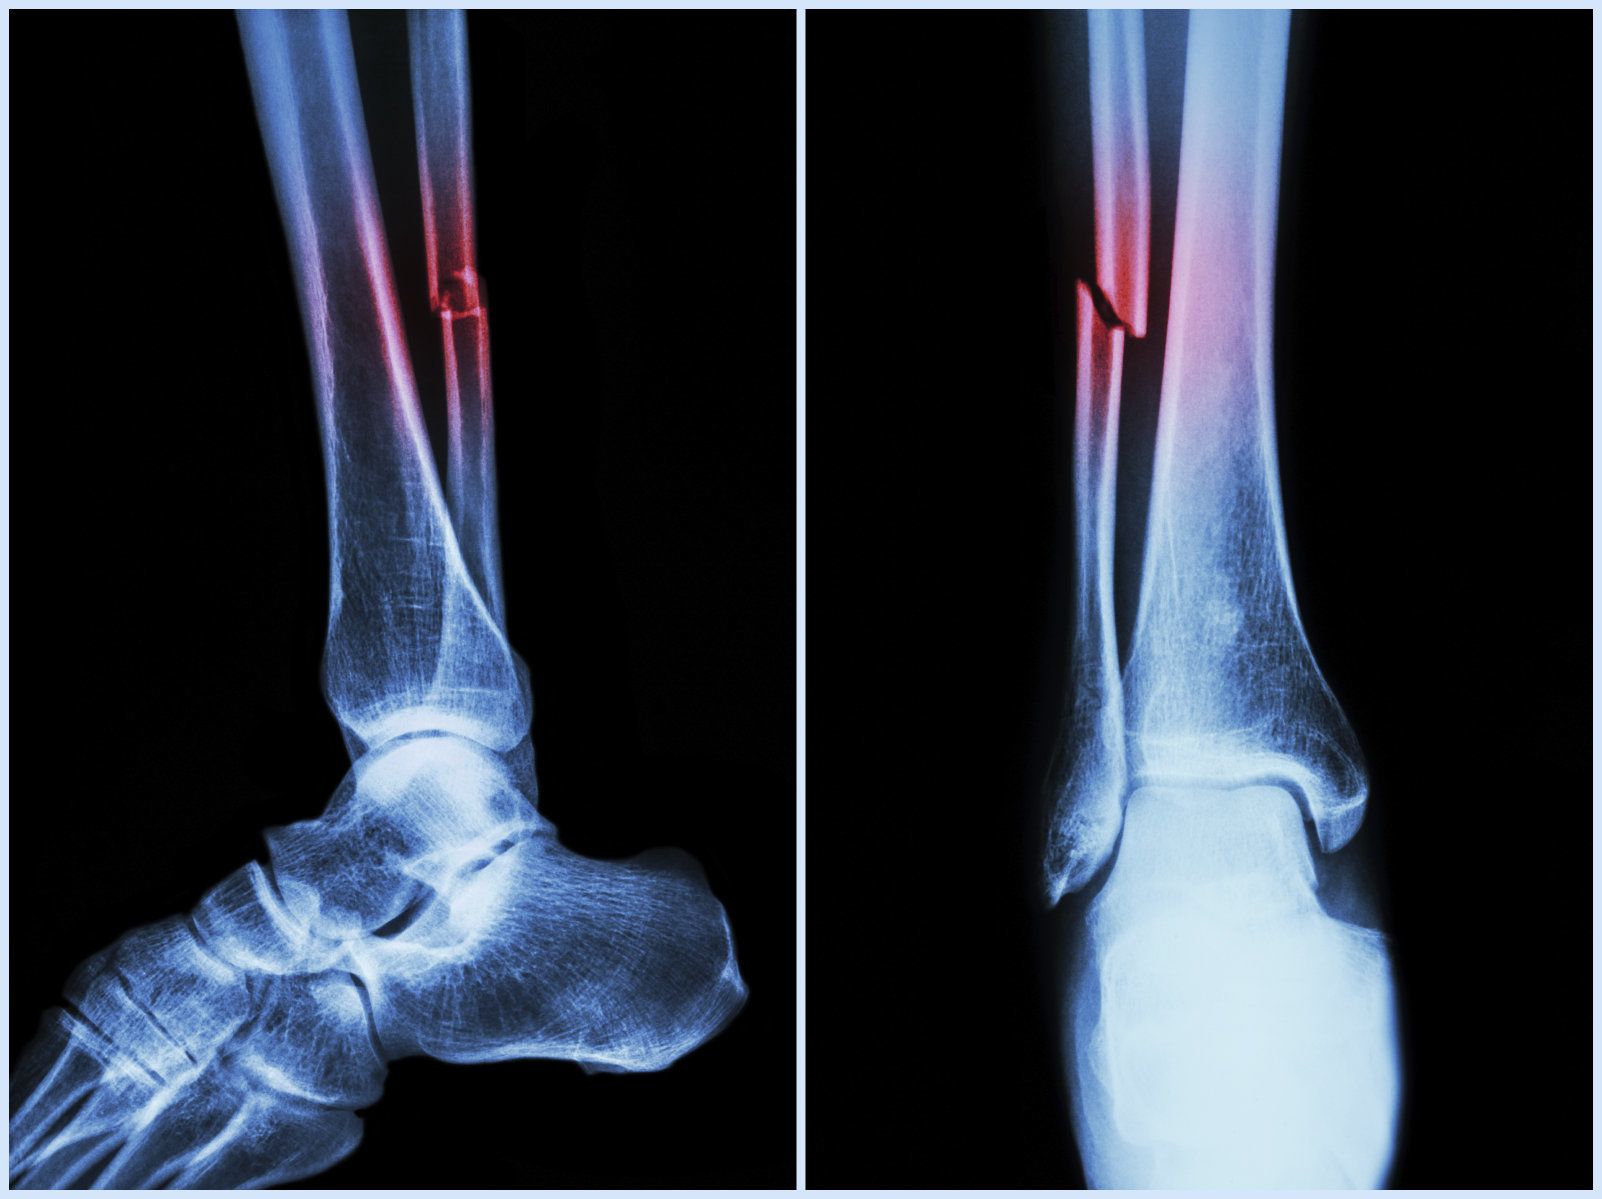

Fractures: Types and Treatment

The word “Fracture” implies to broken bone. A bone may get fractured completely or partially and it is caused commonly from trauma due to fall, motor vehicle accident or sports. Thinning of the bone due to osteoporosis in the elderly can cause the bone to break easily. Overuse injury is a common cause of stress fractures in athletes.

Types of fractures include:

• Simple fractures in which the fractured pieces of bone are well aligned and stable.

• Unstable fractures are those in which fragments of the broken bone are misaligned and displaced.

• Open (compound) fractures are severe fractures in which the broken bones cut through the skin. This type of fracture is more prone to infection and requires immediate medical attention.

• Greenstick fractures: This is a unique fracture in children that involves bending of one side of the bone without any break in the bone.